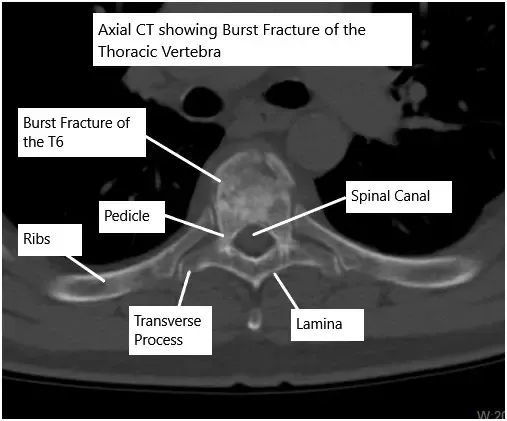

CT scan of the thoracic spine showing a burst fracture of the T6 vertebra.

- Burst fractures: The vertebra shatters into multiple pieces, sometimes pressing into the spinal canal.